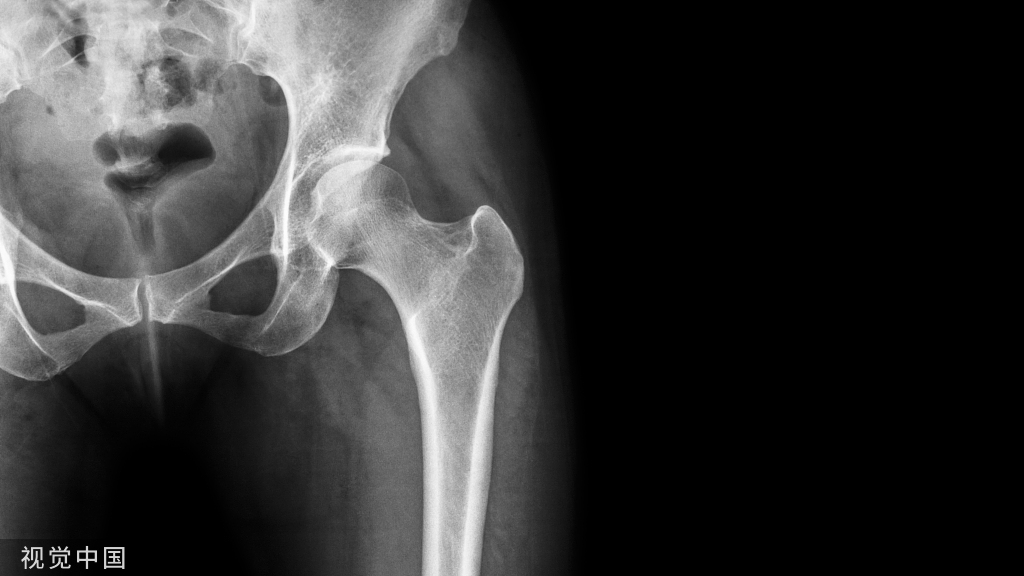

教学病例:踝关节X线片!